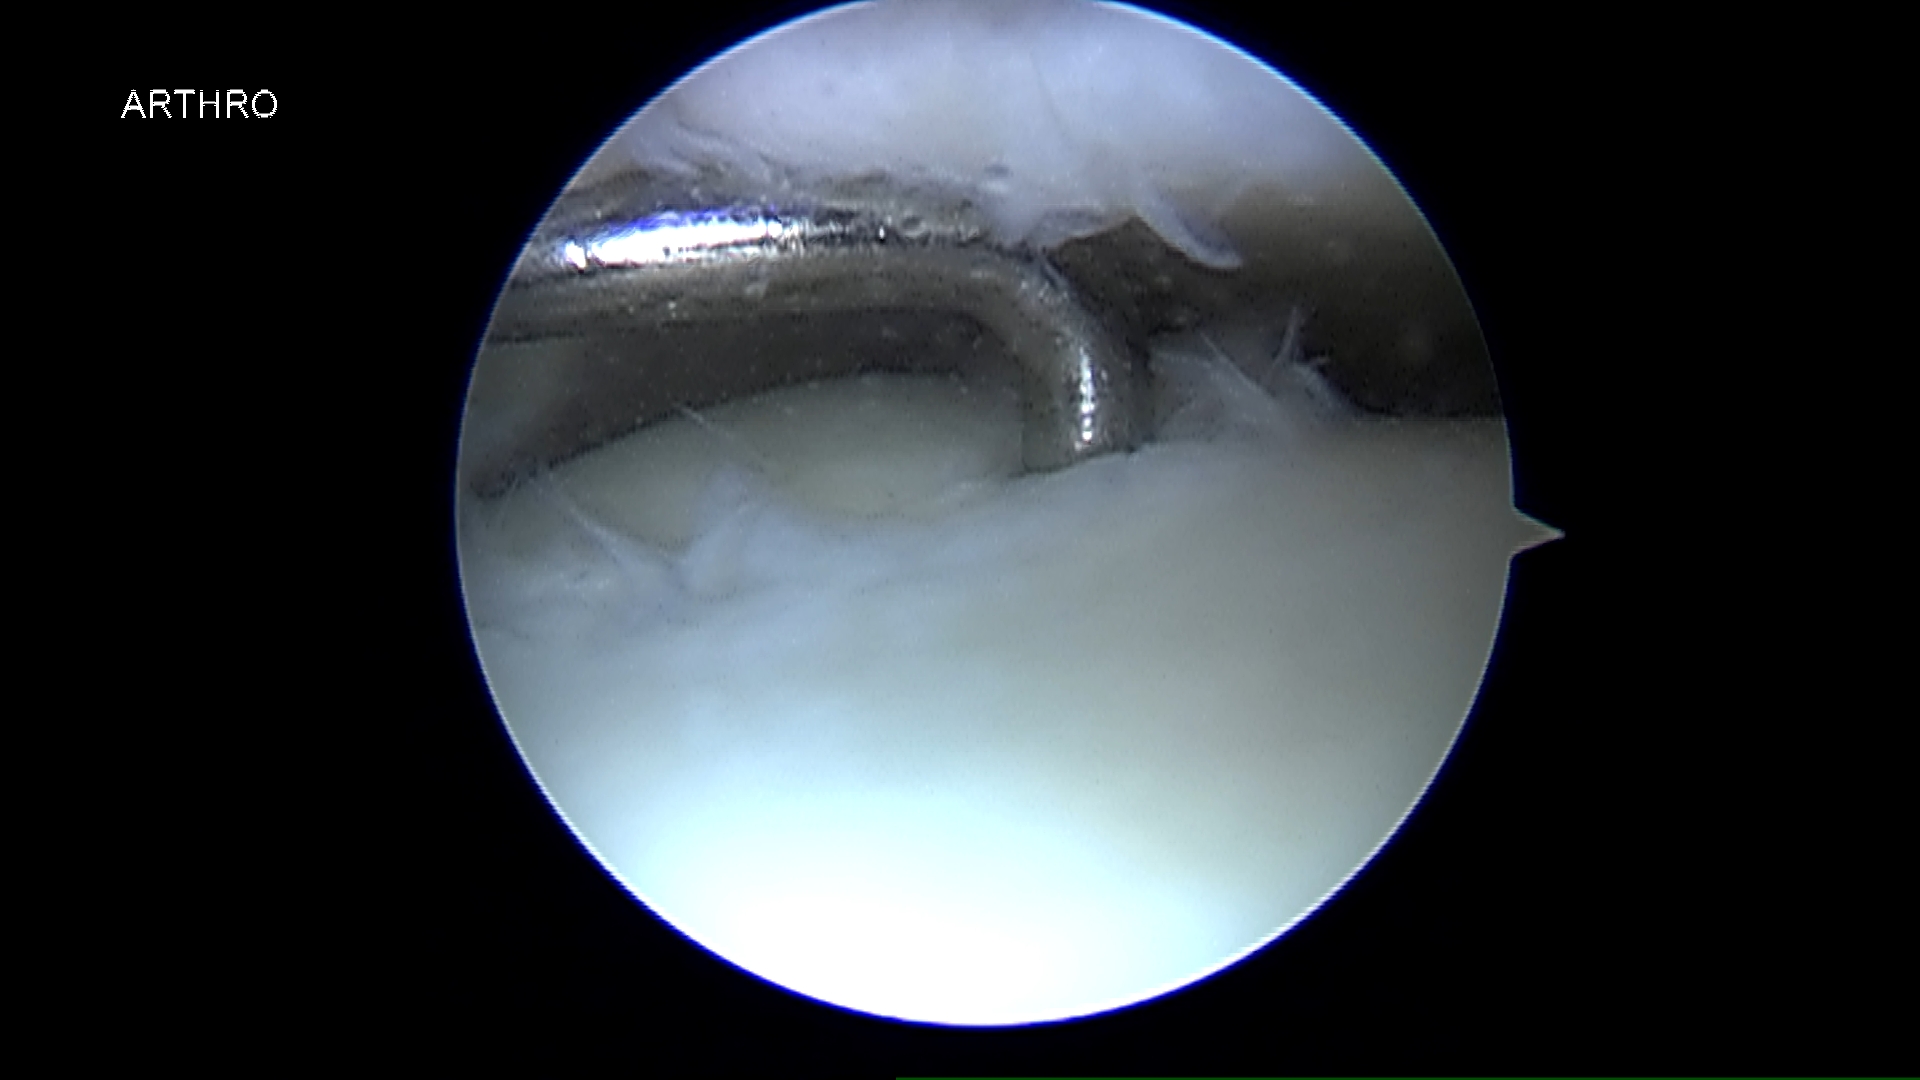

Lesiones osteocondrales

Las lesiones osteocondrales son las que afectan al cartílago y hueso de las articulaciones.

Son frecuentes y especialmente graves las que afectan al astrágalo ya que el cartílago no tiene capacidad por sí mismo de regeneración.

La causa generalmente suele ser un traumatismo aunque muchas veces no es importante, pudiendo desencadenarse por microtraumatismos repetidos (torceduras, esguinces, etc.).

El paciente suele referir dolor en el tobillo, a veces con inflamación y con sensación de fallo o poca estabilidad. Para el diagnóstico es imprescindible una minuciosa exploración, ya que en muchas ocasiones existen factores biomecánicos favorecedores de esta patología, como son alteraciones en el eje del pie o la pierna o inestabilidades por fallo de los ligamentos. El diagnóstico clínico deberá correlacionarse con exámenes radiológicos, de resonancia magnética y/o TAC para aconsejar y planificar el tratamiento más adecuado según cada caso.

Existen diversas técnicas para el tratamiento de la lesión osteocondral, desde la reparación mediante estimulación ósea por microperforaciones, a la aplicación de técnicas avanzadas de regeneración mediante cultivo de condrocitos o de sustitución mediante injerto osteocondral. La indicación de cada una debe ser individualizada según el paciente, la edad, el tamaño y profundidad de la lesión. En ocasiones deberá corregirse además la existencia de una alteración en el eje de apoyo del pie o la reparación ligamentaria.

Artroscopia y Endoscopia de Tobillo

Técnica quirúrgica semi-invasiva que empleamos para el diagnóstico y tratamiento de inestabilidades de tobillo, lesiones osteocondrales, soporte en fracturas, tendinopatías y otros procedimientos quirúrgicos.